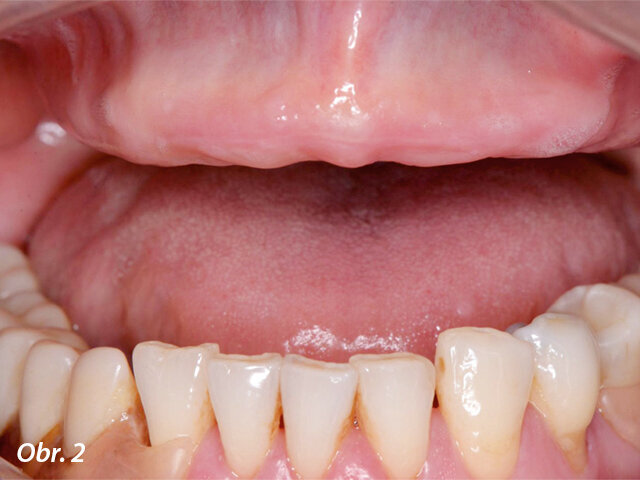

Pacientka se dostavila na naši kliniku se snímatelnou náhradou v horní čelisti (obr. 1), která vykazovala nízkou stabilitu a nevyhovující žvýkací funkci. Pacientka si stěžovala i na estetiku, ale funkční aspekt byl pro ni rozhodující. Po klinickém vyšetření (obr. 2–3) a CBCT analýze jsme naplánovali zavedení šesti implantátů Straumann BLX jako oporu pro fixní můstek v rozsahu celého oblouku (obr. 4). Provizorní můstek byl vyroben před zavedením implantátů. K provedení statické řízené operace byla vytištěna chirurgická šablona.